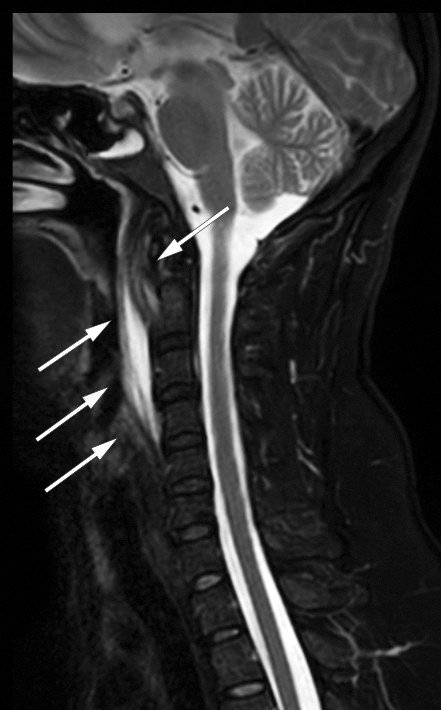

Det ble supplert med MR-undersøkelse av cervikalcolumna, som bekreftet væske i det retrofaryngeale rommet og ødem i bløtvevet prevertebralt, men utelukket spondylodiskitt (figur 2). Kalsifiserende tendinitt ble vurdert som differensialdiagnose, men da pasientens smerter forverret seg, ble hun innlagt på øre-nese-hals-avdeling for videre utredning. På dette tidspunktet hadde hun nærmest ingen motilitet i nakken og fikk nesten ikke i seg mat eller drikke på grunn av svelgsmerter. Ved undersøkelse var det ingen utbukning i farynks slik man ville forvente ved abscess, og det var fremdeles ingen leukocytose. Man startet behandling for tendinitt med diklofenak 50 mg × 3 per os, men valgte også å dekke for infeksjon med klindamycin 300 mg × 4 intravenøst. Allerede neste dag var pasientens symptomer gått betraktelig tilbake i form av bedret nakkebevegelighet og reduserte smerter, med raskere respons enn man ville forvente ved retrofaryngeal abscess. Antibiotikabehandlingen ble derfor seponert, da det ikke lenger var mistanke om infeksjon. På tredje dag, etter ett døgn uten antibiotika, var CRP-verdien halvert, og pasienten kunne utskrives med diagnosen kalsifiserende tendinitt i musculus longus colli og fortsatt behandling med diklofenak 50 mg × 3 per os i en uke. Blodkulturer tatt ved innkomst var negative (svar tilgjengelig etter utskrivingen). Det var ikke behov for videre oppfølging etter dette.

Mengden kalk kan variere og korresponderer ikke med grad av inflammasjon (2). Det kan foreligge sekundære inflammatoriske forandringer som væske retrofaryngealt og ødem i det prevertebrale bløtvevet, som påvist på både CT og MR hos denne pasienten (figur 1 og 2). Ved retrofaryngeal abscess vil man forvente kontrastoppladning rundt væskesjiktet, eventuelt gasslokulamenter og forstørrete lokale lymfeknuter, i motsetning til ved kalsifiserende tendinitt, hvor dette er fraværende (2, 4). Hos denne pasienten ble det likevel gitt antibiotika, da en infeksiøs prosess ikke kunne utelukkes helt. Antibiotikabehandlingen ble riktignok seponert, da pasientens symptomer gikk raskere tilbake enn man ville forvente ved infeksjon, noe som styrket mistanken om kalsifiserende tendinitt.

I dette tilfellet ble det også utført MR av cervikalcolumna for å utelukke spondylodiskitt. MR har høy sensitivitet når det gjelder å fremstille de inflammatoriske forandringene i og rundt m. longus colli, men har dårligere sensitivitet enn CT når det gjelder å fremstille forkalkningene, og er derfor ikke førstevalg (2).